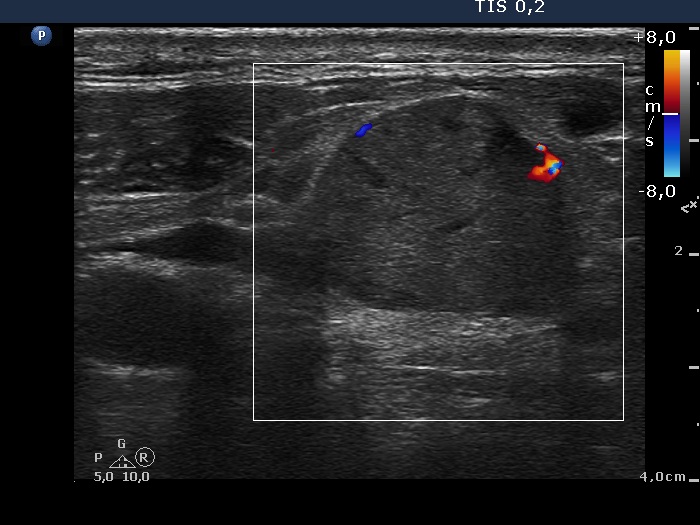

Ultrasonography revealed that the palpable mass contained the enlarged left thyroid composed of a large hypoechogenic nodule with irregular borders and multiple irregular lymph nodes in the left side of the neck.